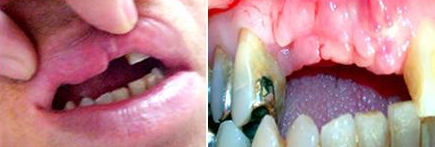

CASO CLÍNICO NÚMERO 2833.

Caso de epítese (gengiva artificial de porcelana).

Situação que o paciente se apresentou no consultório para colocação de implantes e restabelecimento da estética e função dos dentes. Como o tecido ósseo havia sido reabsorvido, para a realização dos implantes, enxerto de ósseo e plasma rico em plaquetas (PRP) teve que ser realizado. Na fotografia vemos os parafusos, fixando os blocos de osso que colocados, e recobertos com PRP (Fotos).